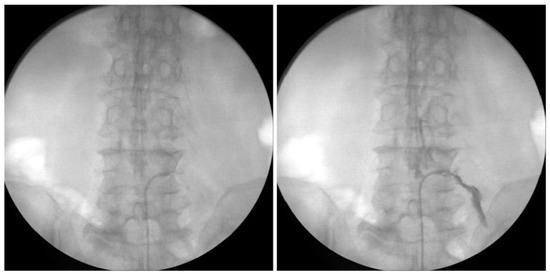

2.4. Endoscopic Epidural Neuroplasty

2.5. PEN with Steering Catheter